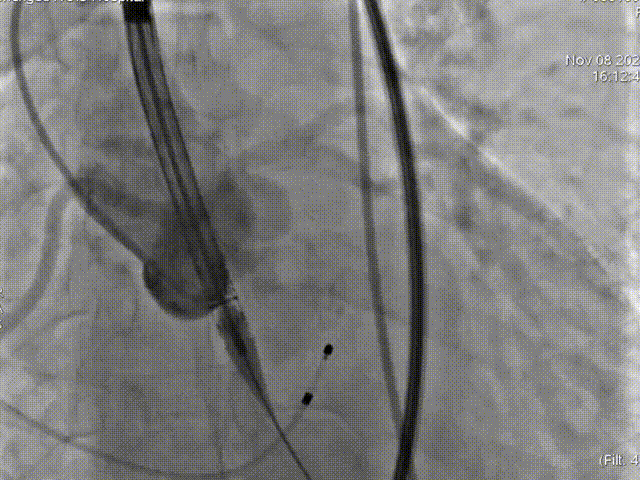

第二次释放位置良好

瓣膜打折

球囊后扩

最终位置完美,无瓣周漏

术后造影及超声探查未见瓣周漏,跨瓣压差由术前70mmHg降为8mmHg,术中及术后未出现相关并发症,手术圆满完成。